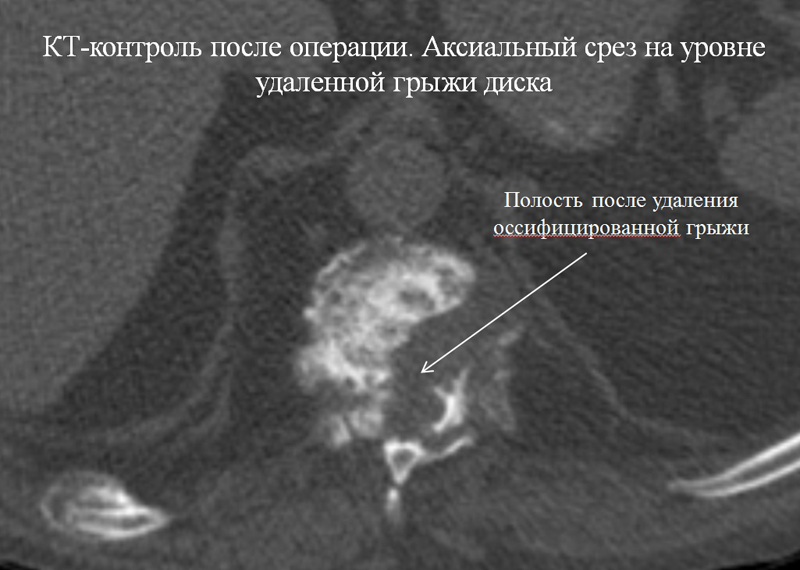

24 апреля 2018 года комбинированной бригадой хирургов (торакальных и нейрохирургов) выполнена операция по удалению оссифицированной грыжи межпозвонкового диска с компрессией спинного мозга на грудном уровне позвоночника.

Первым этапом через плевральную полость выполнили робот-ассистированный доступ к передним отделам позвоночника, с прецизионным выделением головки ребра, тела позвонка и межпозвонкового диска, резекцией головки ребра. Вторым этапом торакоскопически с использованием ультразвукового ножа удалили оссифицированную грыжу диска. Послеоперационный период гладкий, пациент выписан через 5 дней для продолжения лечения у невролога по месту жительства.